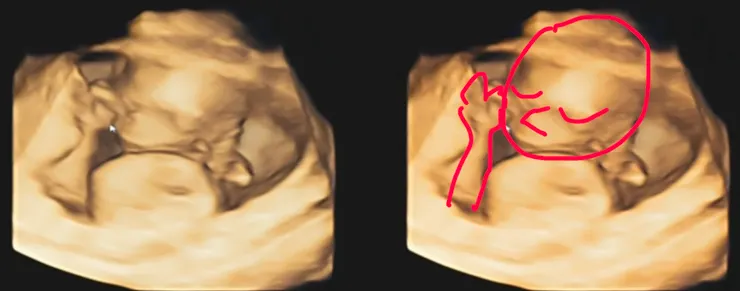

16w+3d已經可以從3D照片看出一些端倪